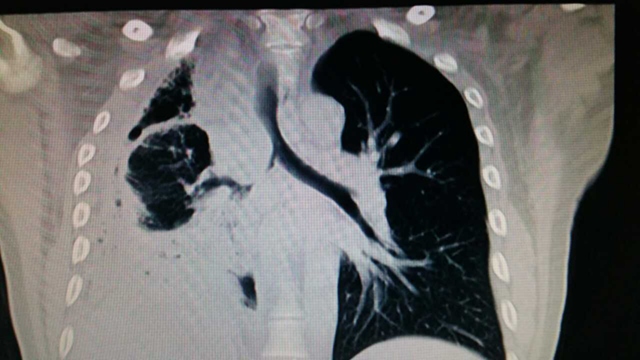

。气管镜提示:距隆突2cm气管右后侧壁可见一菜花样肿块突入气管腔,并向下侵犯右主支气管,右主支气管大部分阻塞。CT提示:气管肿瘤,右侧肺不张,伴有液气胸,肺实变,胸膜增厚明显。经CT下穿刺提示:神经鞘瘤。

术前胸部CT冠状位片

术前全科经多次讨论:患者年轻,病变良性可能性大,手术有彻底治愈可能;但因位置特殊,病史较长,手术难度较大,术中、术后风险较高,手术价值大。从科主任到主管医生和全科对此都予以高度重视,尽快完成了必要的检查,雷光焰主任又与国内胸外科专家多次远程讨论,进行了CT气管三维重建,并通过3D打印技术进行了肿瘤与气管、肺的立体模型构建,预演术中的精确切除、气管瓣的设计和气管的重建等,对手术的复杂性及困难点给予充分评估。最后又组织了医务科、医疗纠纷办、麻醉科、重症医学科和护理部的专家进行了术前重大手术讨论,就病变的精确切除、气管瓣的设计、气管的修复重建、术中换气管配合、术后监护护理及可能出现的危险情况进行了讨论,准备了多套手术方案及相应补救措施和应急预案。